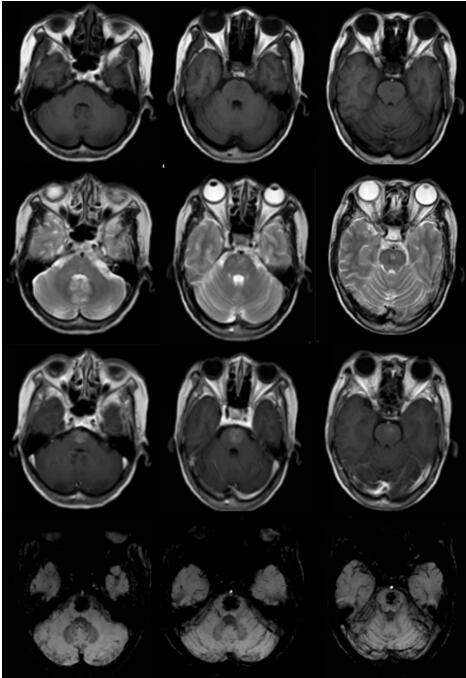

辅助检查: 外院CT、MR:脑干占位性病变,胶质瘤可能性大;双侧额叶、右侧基底节多发小缺血灶。本院半球MRV检查未见异常;MRS序列提示桥脑病变感兴趣区谱线稍欠平稳,其Cho及Cr各峰未见升高或下降,其NA峰未见明显下降;DWI序列提示桥脑病变弥散不受限;SWI序列提示:1.桥脑病变考虑为血管源性病变,血管畸形(毛细血管扩张症)可能;2.左侧放射冠区含铁血黄素沉积(见图1)。2018年7月19日本院DSA检査提示:右侧颈内动脉交通段瘤样突起,呈囊状,大小约0.5mm*1.0mm。余脑血管造影未见明显异常。

图1.可见T1WI表现为稍低信号、T2WI 表现为稍高信号,增强表现为稍高信号,磁敏感加权成像(SWI)表现为类圆形极低信号,边界清楚,与周围组织对比鲜明。